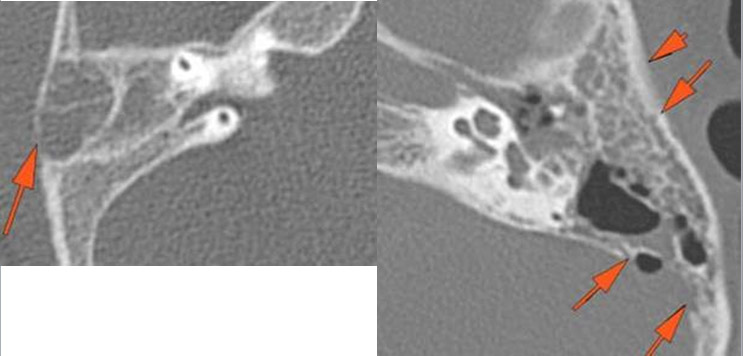

The external cortex of the mastoid process is eroded. [Yes/No]

There is a subperiosteal abscess along the outer margin of the mastoid portion of the temporal bone. [Yes/No]

The mastoid septae are eroded. [Yes/No]